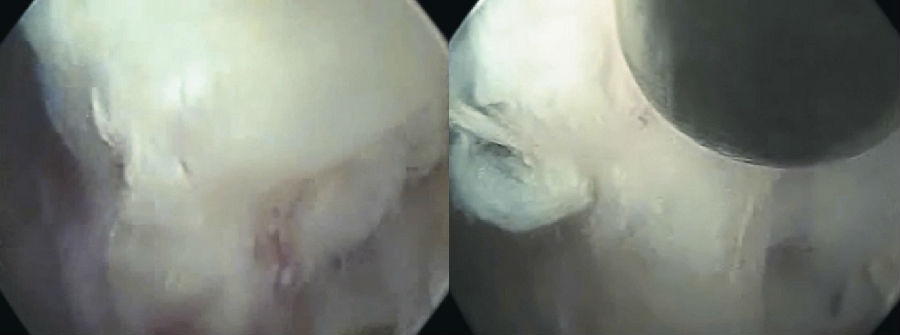

8. 镜下操作

采用一次性双极射频手术刀头、Punch钳、小直钳、磨钻依次切除或修整部分肥厚或钙化的黄韧带、椎体后缘增生的骨赘、椎体后缘对神经根造成压迫的外层纤维环及其边缘的硬化或骨化结构、与后纵韧带粘连的增生结缔组织,对神经根背侧和腹侧进行全面的减压松解,特别是神经根下方的微小硬化性组织。(图16~图21)

图16 内镜下显示套管内视野中间纤维环

图17-图20 内镜下显示套管内视野中间纤维环;内镜下小直钳取髓核;取出部分髓核后张力下降,神经张力间接下降;转动工作套管显露硬膜囊和周围组织

9. 双极射频使破裂的纤维环消融皱缩成形。观察可见硬膜囊自主搏动,神经根表面血运明显改善,血管充盈,神经根复位,术中行直腿抬高试验,可见神经根被牵拉后滑移自如。(图22、图23)

图21-图24 取出的髓核组织(中间部分硬化);下行根头端减压;硬膜囊、下行根减压后神经松解,博动良好;手术切口(大小约8mm)